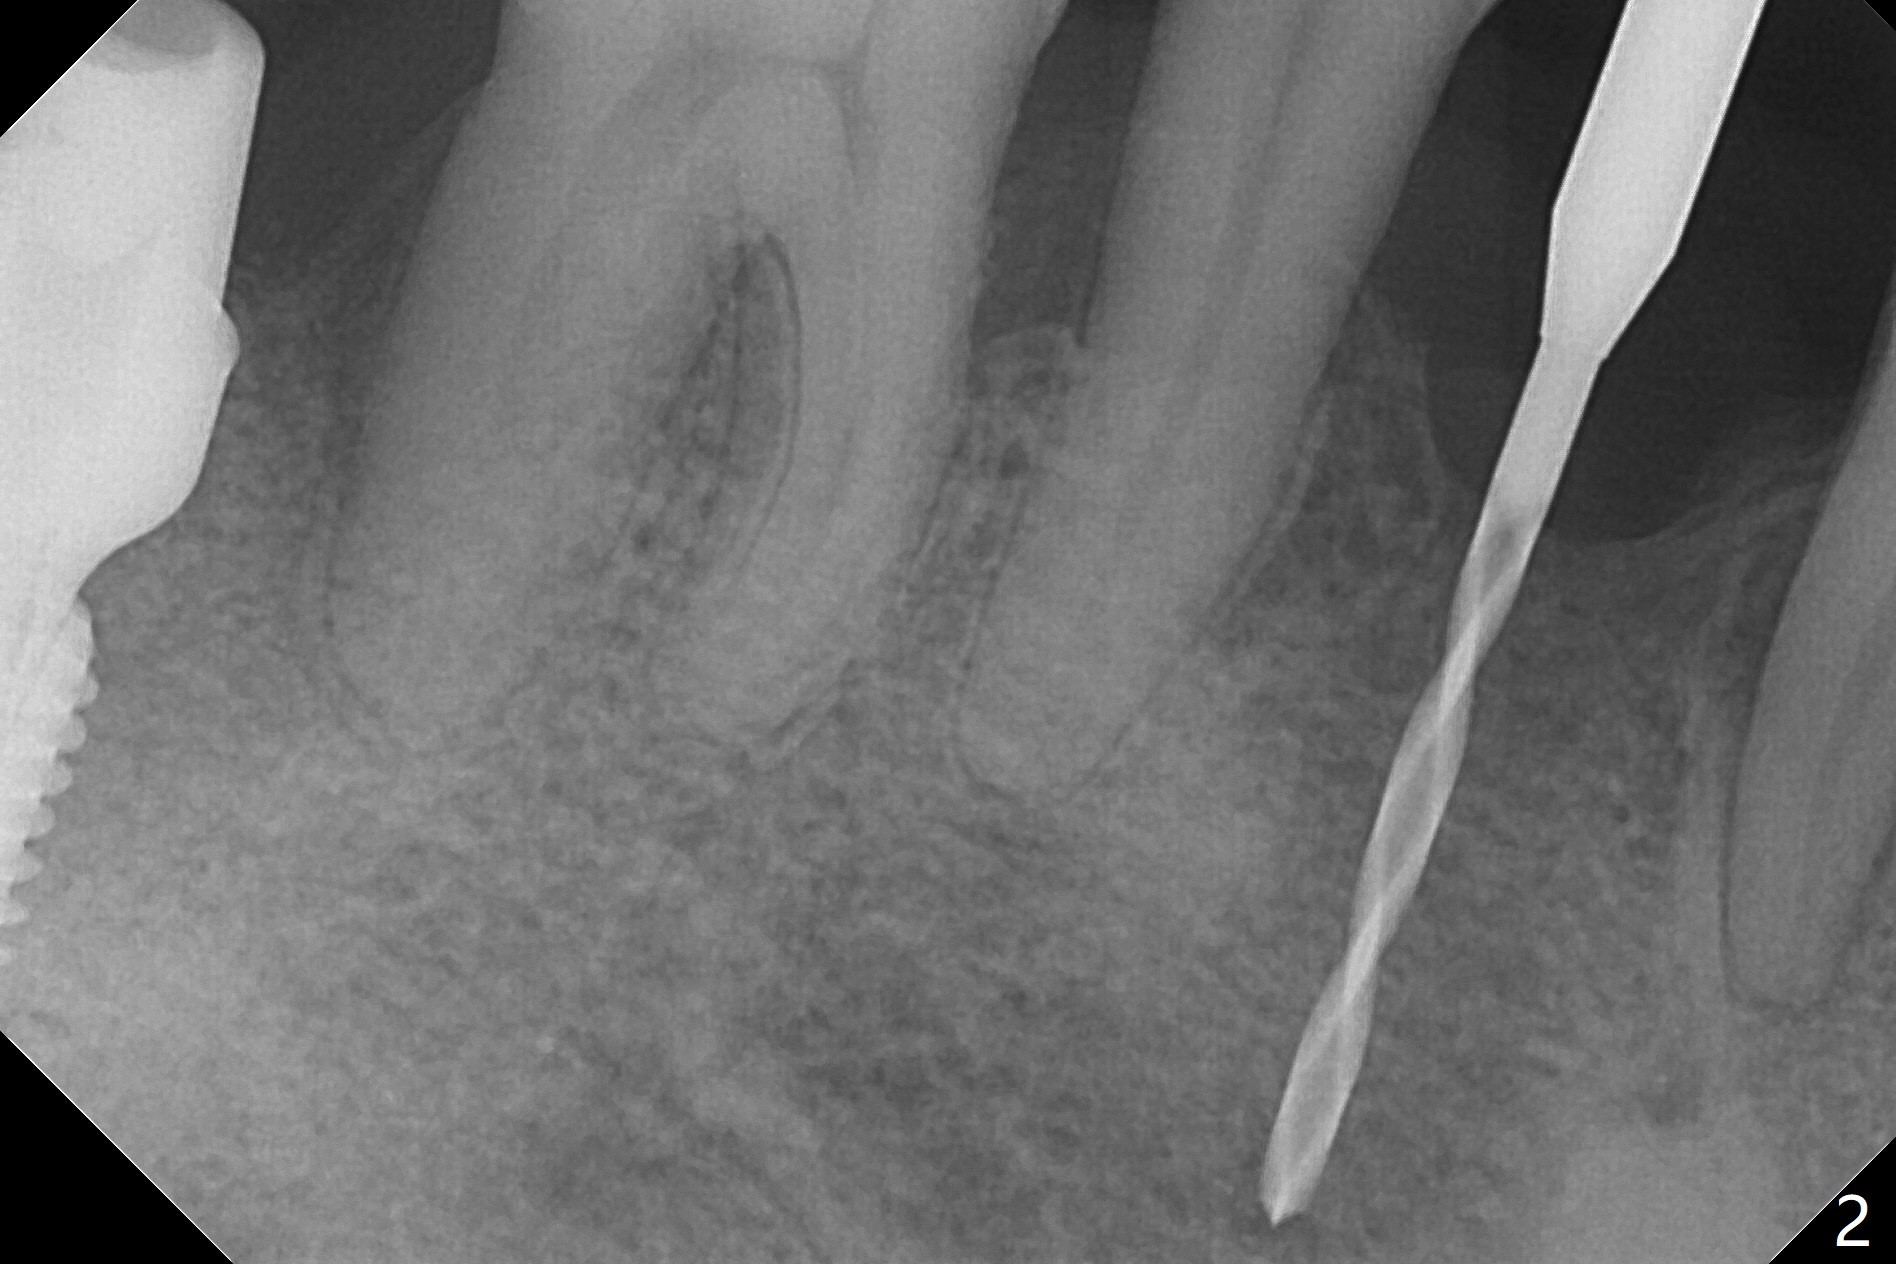

When flaps are raised at #28, the ridge appears to be narrow. Severe ridge resorption occurs 1-2 years post exfoliation. After ridge reduction, osteotomy is initiated mesially (Fig.1 (broken drill as a parallel pin)). A new osteotomy is going to be initiated as indicated by a blue line in Fig.1. It is done close to what is expected (Fig.2). When a 2.5x10(4) mm 1-piece implant is placed <20 Ncm, a major concern is where the Mental Loop is. To answer the question, intraop CBCT is taken (Fig.4). It appears that the ridge has not resorbed. If palpate more lingually (Fig.4 white <), the ridge would be found not so narrow. Preop and intraop panoramic X-ray film show sufficient bone height at the site (Fig.5,6). Low torque may be associated with low postop bone resorption, but it will take long to restore the implant.